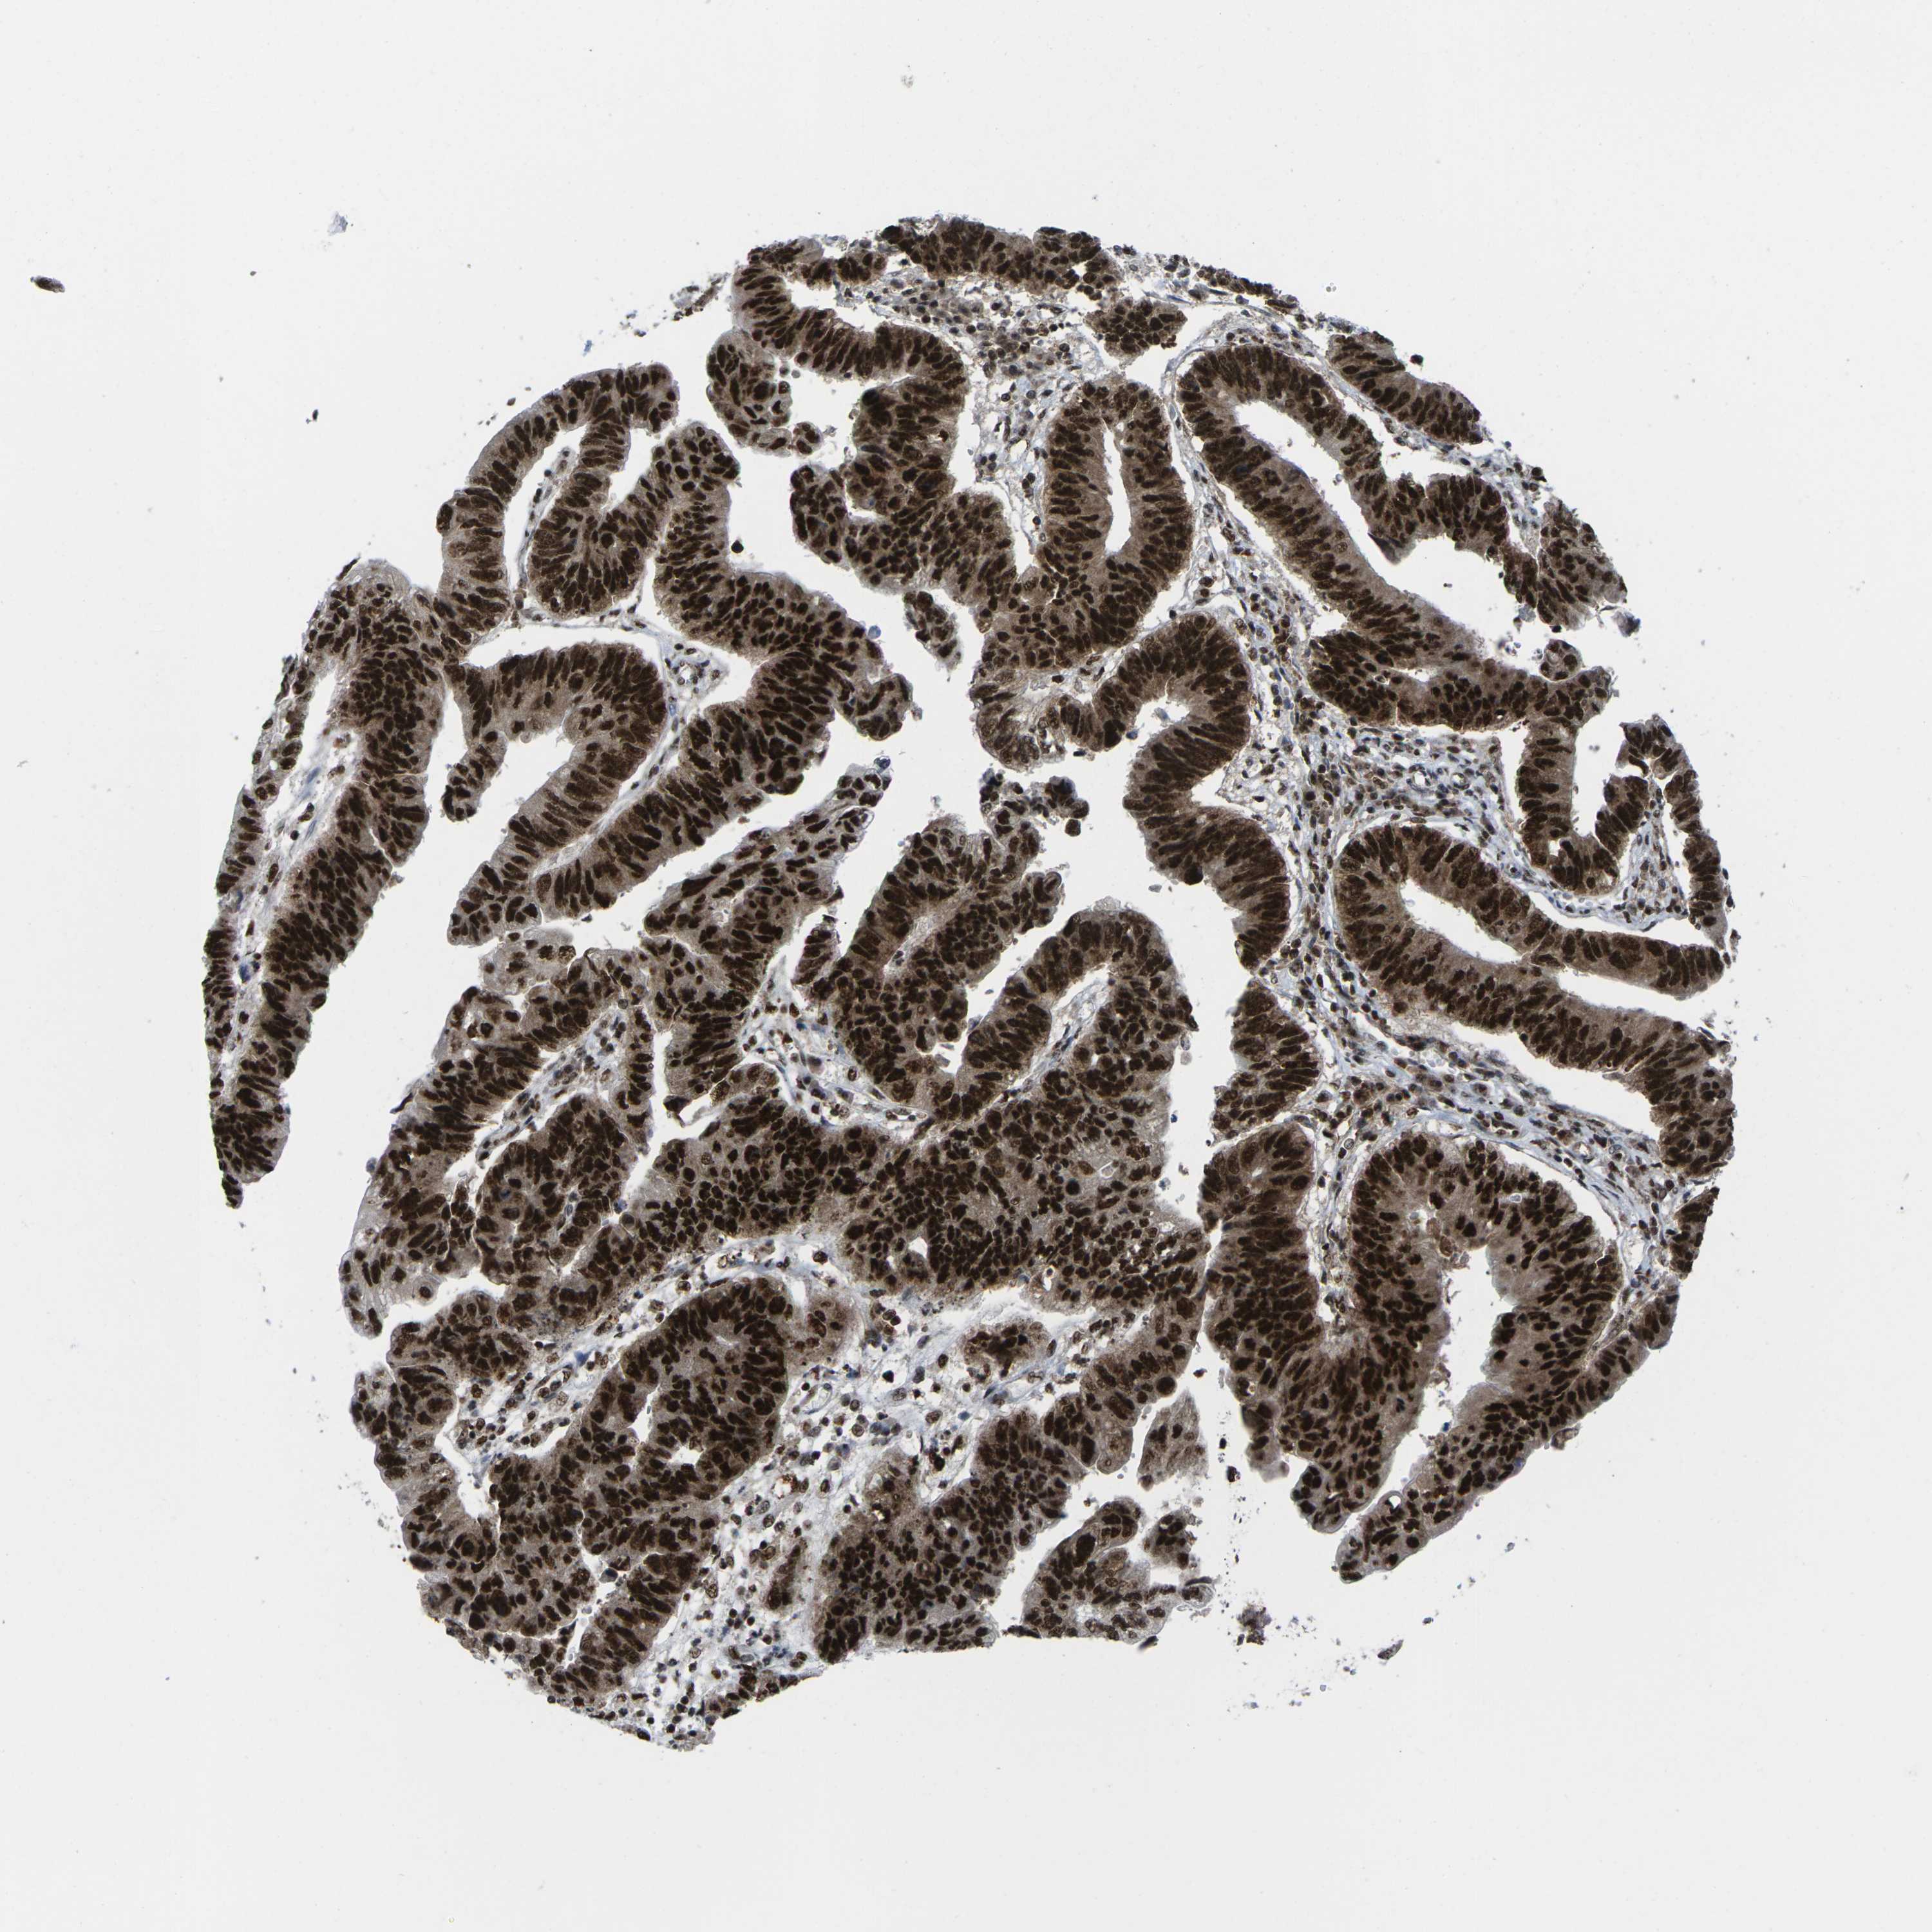

STOMACH CANCER - Protein expressioni

A mouse-over function shows sample information and annotation data. Click on an image to view it in a full screen mode. Samples can be filtered based on level of antibody staining by selecting one or several of the following categories: high, medium, low and not detected. The assay and annotation is described here.

Antibody stainingi

Antibody staining in the annotated cell types in the current human tissue is reported as not detected, low, medium, or high, based on conventional immunohistochemistry profiling in selected tissues. This score is based on the combination of the staining intensity and fraction of stained cells.

Each image is clickable and will lead to virtual microscopy that enables deeper exploration of all samples and also displays staining intensity scores, fraction scores and subcellular localization as well as patient and tissue information for each sample.

Antibody HPA043036

Antibody HPA047754

Antibody CAB015425

Staining

High

Medium

Low

Not detected

Intensity

Strong

Moderate

Weak

Negative

Quantity

>75%

75%-25%

<25%

None

Location

Nuclear

Cytoplasmic/membranous

Cytoplasmic/membranous,nuclear

Adenocarcinoma, NOS

Adenocarcinoma, High grade